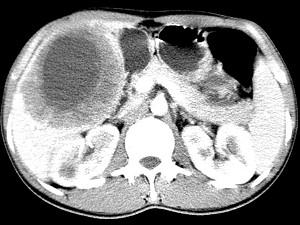

问题 女,61岁,上腹部疼痛一个月,食欲减退,消瘦,CT所见如图,最可能的诊断是 ( )

选项 A、肝包虫病 B、原发性肝癌 C、肝转移瘤 D、胃癌肝转移 E、肝脓肿

答案 D